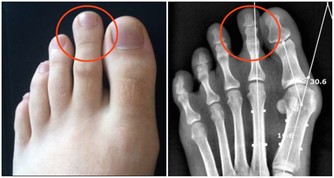

運動少,血管垃圾多正常人皮膚上每平方毫米約有600根毛細血管,平時只開放100—200根,多運動能讓更多的毛細血管開放,促進血液微循環;而長期不運動,血管內的垃圾會逐漸累積,形成粥樣硬化斑塊這個“不定時炸彈”,還會影響到毛細血管供血,並且隨時可能被引爆。